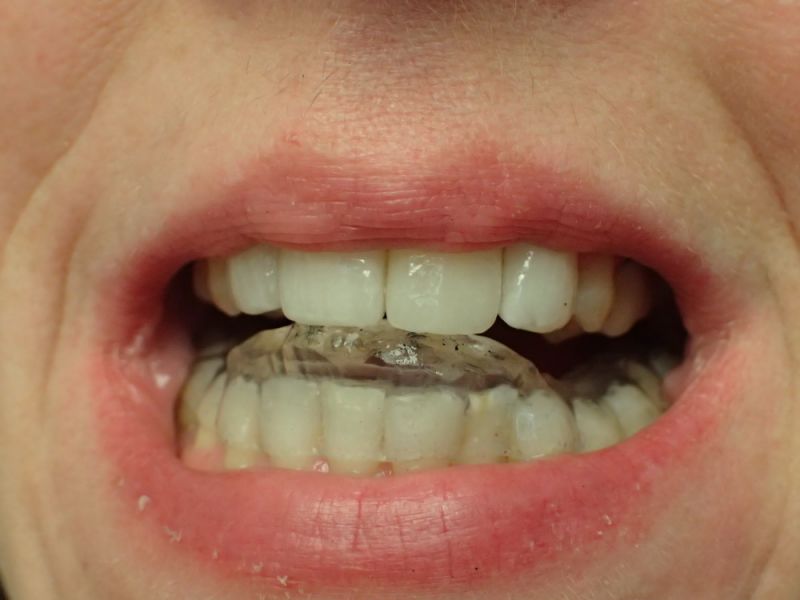

Patientin von der dänischen Grenze erhält einen adjustierten Aufbissbehelf

Sollte über die Funktionsdiagnostik hinaus in diesem Fall eine Funktionstherapie zustande kommen, wäre deren Ziel nicht nur die Beseitigung/Linderung der bekannten funktoinellen Beschwerden, sondern darüber hinaus der Stopp des anhaltenden alveolären Knochenabbaus.